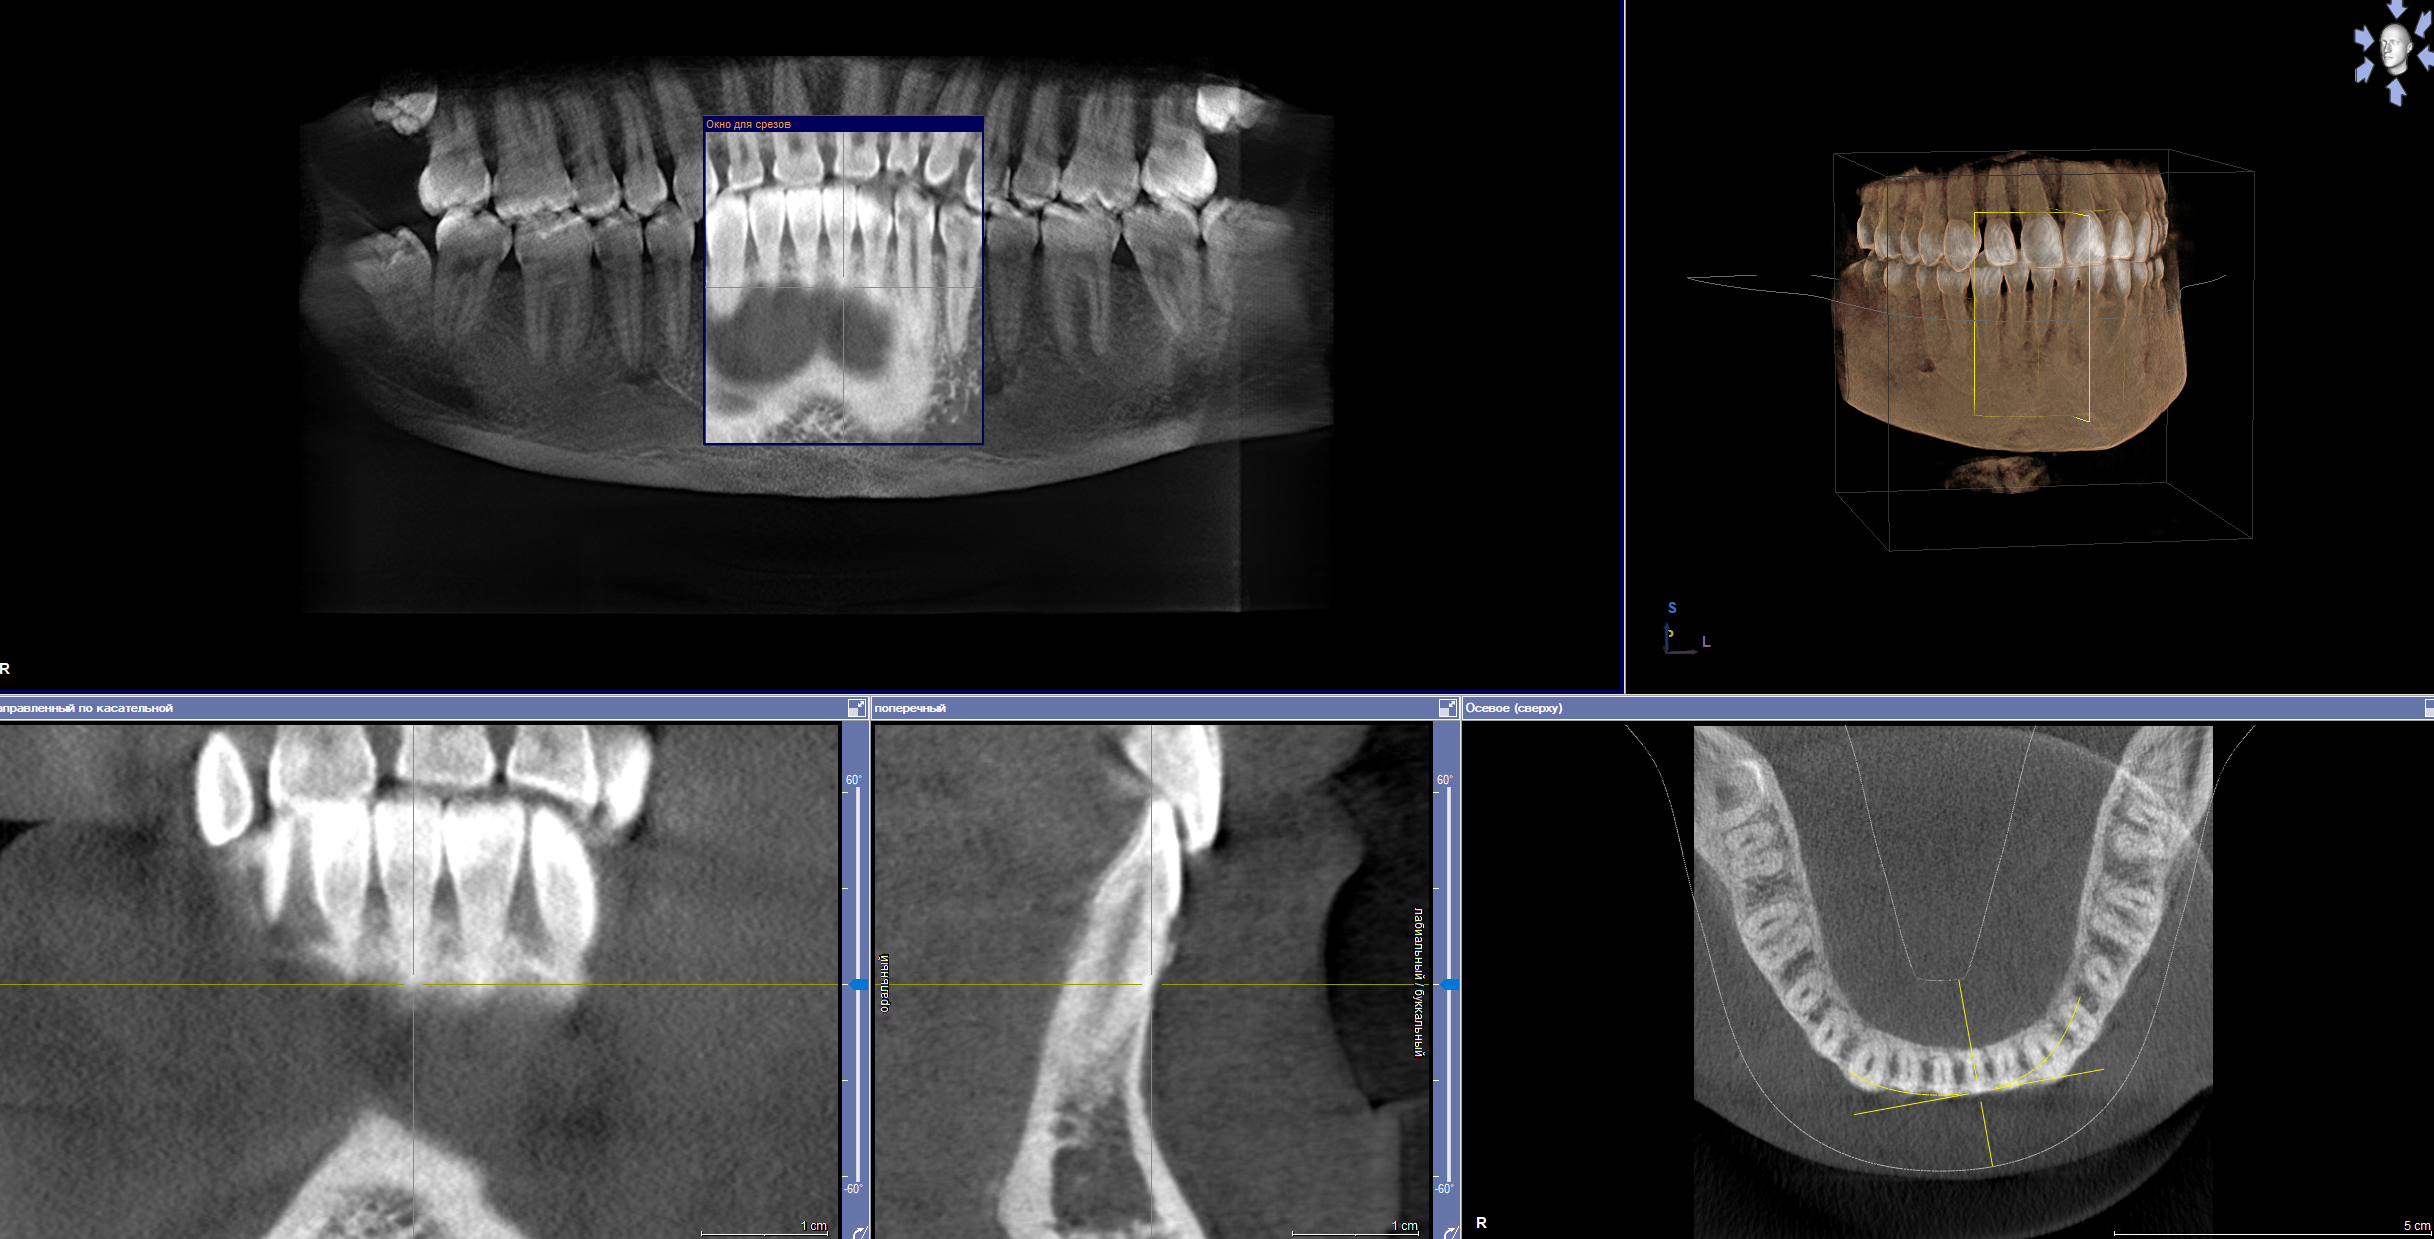

Сделали мне цистэктомию с удалением зуба переднего (резца), консервативное лечение не помогло, попутно разъебали всю кость-десну и теперь огромный провал-долина на месте где зуб был. По КТ уже было видно огромную площадь кисты и сразу сказали что костную пластику надо делать, хотели сразу после удаления но хирург разрезав сказала что киста рыхлая и хуевая и не будет делать пластику т.к. высок риск отторжения материала.

Пока что зашила меня и отправила отдыхать, через неделю осмотр, примерно через месяц сказала можно подумать будет над пластикой.

Алсо подскажите мне, нужно ли мне с имплантологом сразу до костной пластики знакомится-работать показаться или пластикой задача челюстно-лицевого хирурга заниматься, а к импантологу уже после месяца через 6 после пластики?